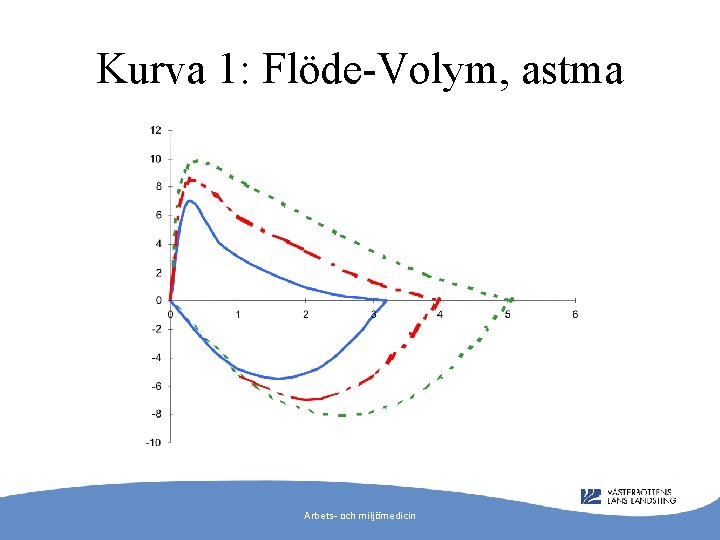

Kurva 1: Flöde-Volym, astma Arbets- och miljömedicin